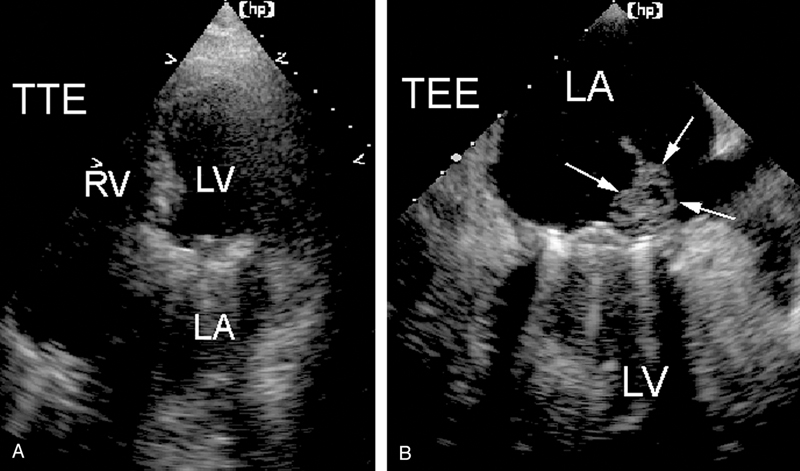

فحوصات تشخيصية لبعض امراض القلب والشرايين التاجية